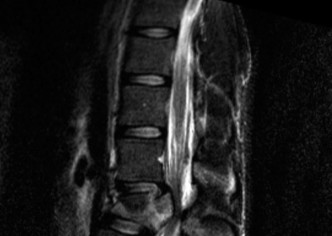

To evaluate the neural elements and the soft tissue structures, a comprehensive MRI of the lumbar spine without contrast was obtained. The T2-weighted sagittal and axial sequences confirmed the Grade 2 anterolisthesis and demonstrated severe bilateral foraminal stenosis at L5-S1. The exiting L5 nerve roots were severely compressed between the hypertrophied, fibrocartilaginous pseudarthrosis tissue of the pars defect dorsally, and the bulging, degenerated L5-S1 disc and superior endplate of S1 ventrally. Furthermore, the MRI revealed Modic Type II changes (fatty replacement of the subchondral bone marrow) in the adjacent vertebral endplates, confirming chronic biomechanical stress and discogenic degeneration. The central canal remained relatively patent, which is characteristic of isthmic spondylolisthesis, as the posterior neural arch is left behind during the anterior translation of the vertebral body.

Clinical & Radiographic Imaging Archive